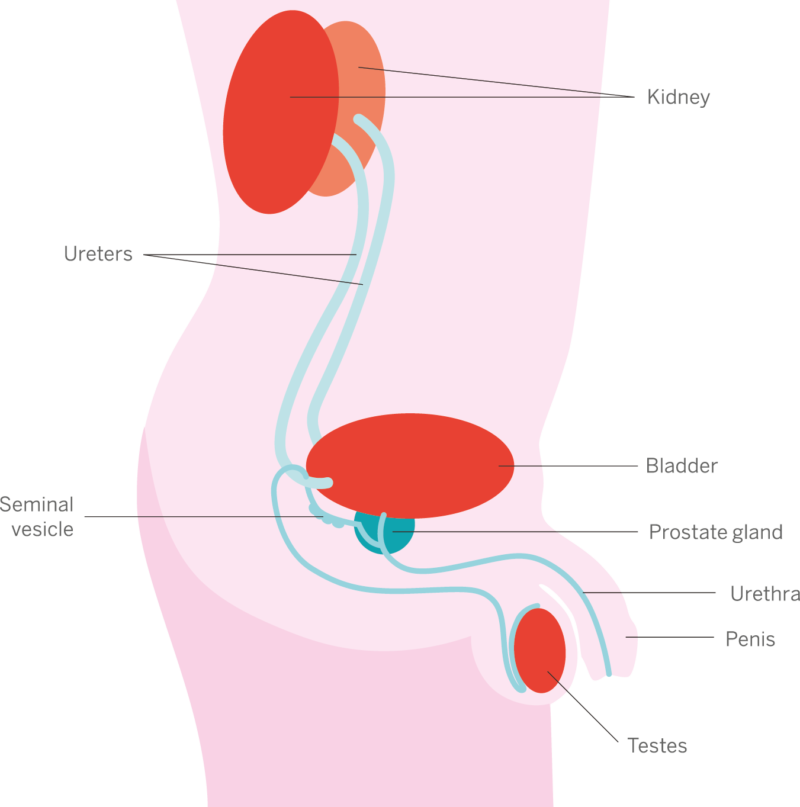

What is Localized or Locally Advanced Prostate Cancer? | PCF

Understanding prostate cancer

The Spread of Prostate Cancer – Prostate Cancer Research Centre